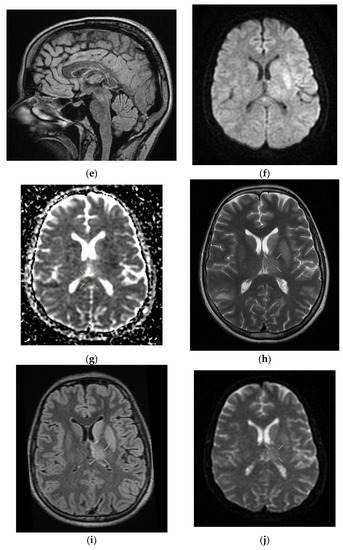

Upon discharge, the neurological examination indicated that the patient was conscious, cooperative, oriented in time and space, without stiffness in the back of the head, no nystagmus, with normal ocular motricity, denial of diplopia, possible deglutition for liquid and solid food, normal speech, no movement deficits, no sensitivity or coordination disorders, and a cutaneous plantar reflex with bilateral flexion. The images of the MRI can be seen below in Figure 2.

Figure 2. Cerebral native and contrast-enhanced MRI and angiography, and CT cerebral venography highlighting the sigmoid sinus and right lateral sinus thrombosis and the inferior sagittal sinus and right sinus thrombosis, associated with right temporal cortical and subcortical subacute hemorrhage, supratentorial recent subacute synchronous lacunar infarct, (cytotoxic and vasogenic) thalamic–lenticular–caudal edema, and supratentorial non-specific demyelinating lesions. Magnetic resonance imaging shows cortico-subcortical subacute hemorrhage in the right temporal lobe (a,b) T1 and T2 hyperintensities. (c) methemoglobin signal. (d) heterogeneous contrast enhancement. (e) supratentorial recent subacute lacunar infarction in a millimeter lesion in hypersignal FLAIR, restrictive in diffusion coefficient. (f,g) supratentorial recent subacute lacunar infarction located in the corpus callosum. (h,i,j,k) cytotoxic and vasogenic edema in diffuse T2 and FLAIR high signal and moderate restriction in diffusion coefficient in the left thalamus. (l,m,n,o) cytotoxic and vasogenic edema in left lenticular-caudate nucleus. (p) right sigmoid and lateral sinuses thrombosis—T1 and T2 hyperintense material, without contrast enhancement. The intravenous post-contrast and native cranio-cerebral MRI examination highlights are as follows: oval globular formations with a non-homogeneous central portion and a periphery with a methemoglobin signal, hyper-intense T1–T2, axial dimensions of 11/10 mm maximally and heterogeneous contrast outlet, along with right temporal cortical and subcortical conglomerates, with extended moderate perilesional oedema; FLAIR hyper-intense millimeter lesions, intense and homogeneous restriction in diffusion and no-contrast outlets in the semioval centers, in the corpus callosum and in the middle temporal gyrus; diffuse signal T2–FLAIR increased in the left and left lenticular–caudal thalamus, with minimum diffusion restriction and no detectable contrast outlets; a few T2–FLAIR hyper-signal millimeter outbreaks, with no diffusion restriction and no corresponding T1, located in the white matter in the periventricular hemisphere and bilateral frontal–parietal subcortical area; normal supra- and infratentorial pericerebral liquid spaces; a symmetric ventricular system, with normal dimensions; structures of the median line in normal position; orbits and orbital content without anomalies; and paranasal sinuses with normal development and pneumatization. Magnetic resonance (MR) cerebral arteriography and venography indicated the following: internal carotid arteries symmetrically disposed, with a normal trajectory and caliber; anterior cerebral arteries and normal average bilaterally detached from the internal carotid, with no areas of stenosis or circumscribed dilation, with a homogeneous intralumenal signal; vertebral arteries, basilar artery, upper cerebral arteries and communicating arteries with a normal trajectory and caliber; hyper-intense T1–T2 material, with a no-contrast outlet, which transversely occupied the sinuses and sigmoid on the right side; and a lesion with the same signal characteristics situated along the right sinus and extended towards the inferior sagittal sinus; the rest of the dural sinuses had no detectable lesions in the sequences observed.